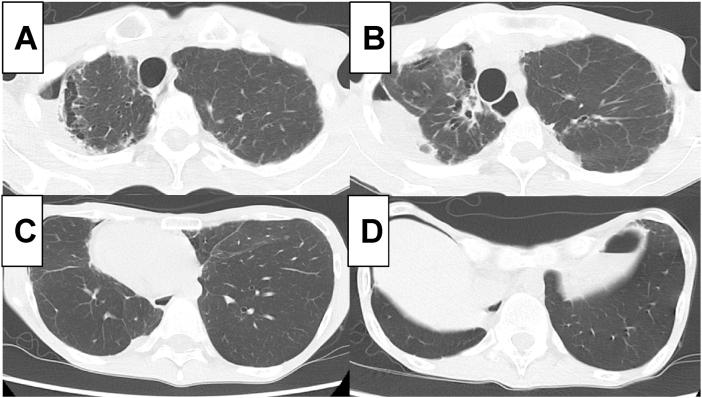

Charcot-Marie-Tooth disease (CMT) is a hereditary peripheral neuropathy characterized by progressive atrophy of distal muscles. Respiratory complications are rare. We present a case of a 49-year-old male with childhood-onset CMT bearing a genetic mutation of MFN2. He had difficulty breathing when he was 46. Imaging examination revealed complications of phrenic nerve paralysis and pneumothorax with a funnel chest. Respiratory function test demonstrated severe restrictive ventilatory impairment. Polysomnography supported the diagnosis of mild sleep apnea syndrome. Noninvasive positive pressure ventilation successfully reduced respiratory symptoms. To our knowledge, this is the first demonstration of multiple respiratory complications in a CMT patient.

夏科-马里-图思病(CMT)是一种遗传性周围神经病,其特征为远端肌肉进行性萎缩。呼吸并发症较为罕见。我们报告一例49岁男性,儿童期起病的CMT,携带MFN2基因突变。他46岁时出现呼吸困难。影像学检查显示膈神经麻痹、气胸合并漏斗胸等并发症。呼吸功能测试显示严重的限制性通气障碍。多导睡眠图支持轻度睡眠呼吸暂停综合征的诊断。无创正压通气成功减轻了呼吸症状。据我们所知,这是首次在CMT患者中证实出现多种呼吸并发症。